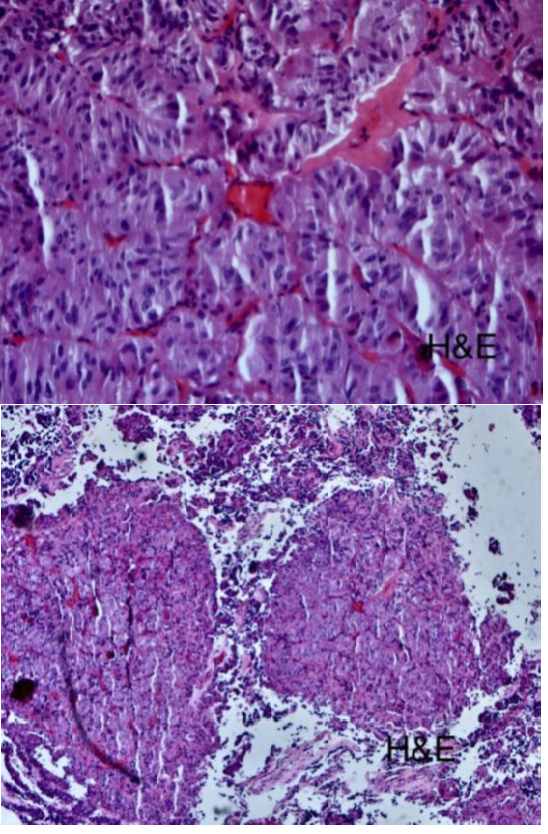

Histopathological staining proved the thyrotropinoma diagnosis (Figure 5) (Figure 6).9

Figure 4 Hematoxylin and eosin stain.

Figure 5 Synaptophysin stain.